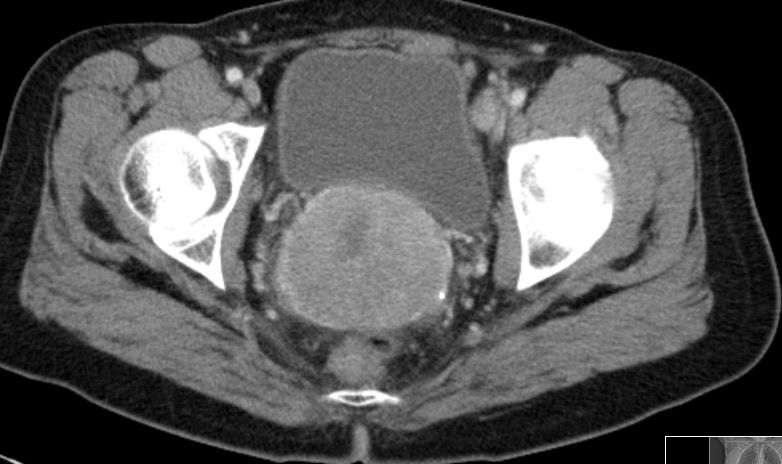

| MRT | 46-jährige Frau mit großem invasivem

Plattenepithelkarzinom der Zervix.![]() |

Im CT suspekter Lymphknoten iliaca externa links

neben der Blase.![]() | ||